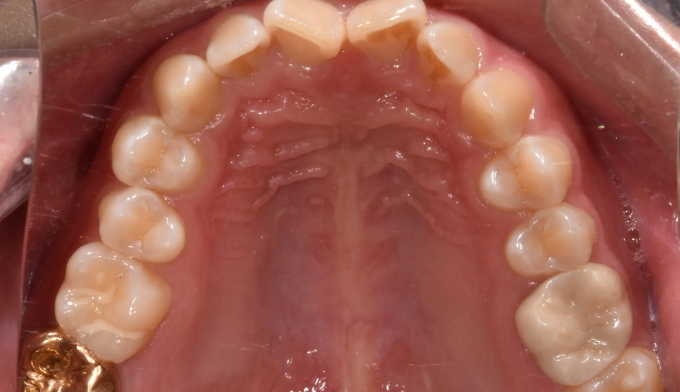

과개교합

과개교합은 앞니를 잇몸안으로 집어넣거나 반대로 어금니를 잇몸밖으로 빼내어 치료하는 방법이 있습니다.

환자의 안모 형태와 입술 두께등을 종합적으로 고려하여 치료방법을 결정합니다.

본 케이스에서는 치아 노출도를 고려하여 윗니를 위로, 아랫니를 아래로 함입하여 과개교합을 치료하였습니다.

교정기간은 총 10개월입니다.